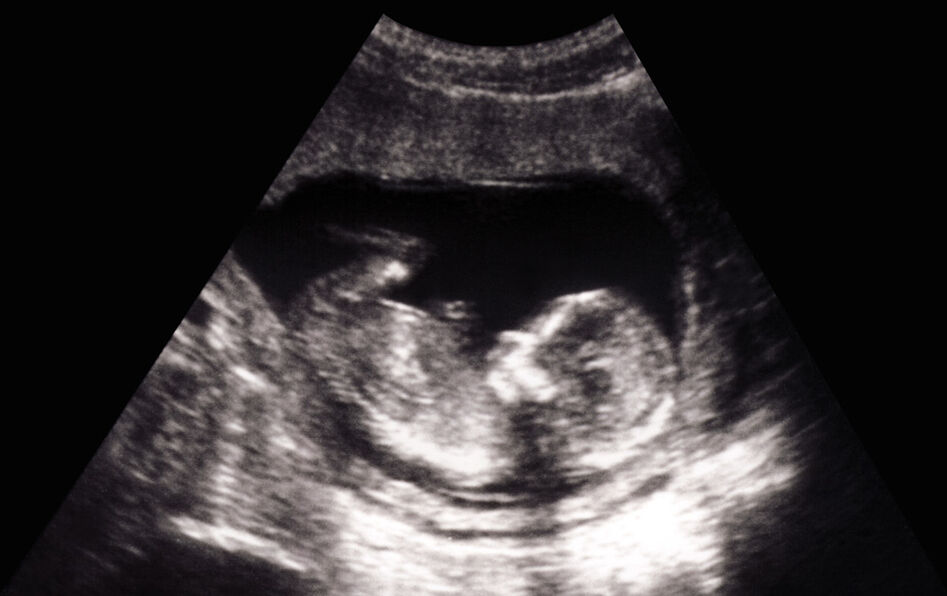

© Mathieukor/iStockphoto

La London’s High Court l’a confirmé début décembre : la cavalière Evie Toombes, atteinte d’une spina bifida, maladie congénitale qui l’oblige à rester régulièrement intubée, n’aurait pas dû venir au monde. Sa pathologie est jugée injuste et cette injustice a un responsable : Philip Mitchell, le médecin qui a indiqué à sa mère qu’il n’était pas « nécessaire » de prendre de l’acide folique – carence qui pourrait avoir engendré la maladie.